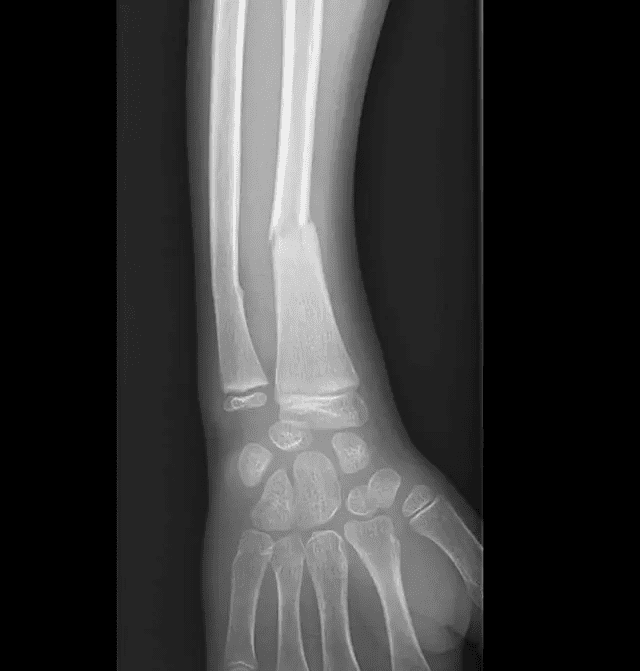

Fracture du radius chez l'enfant

Suivi évolutif de consolidation d'une fracture du radius chez l'enfant